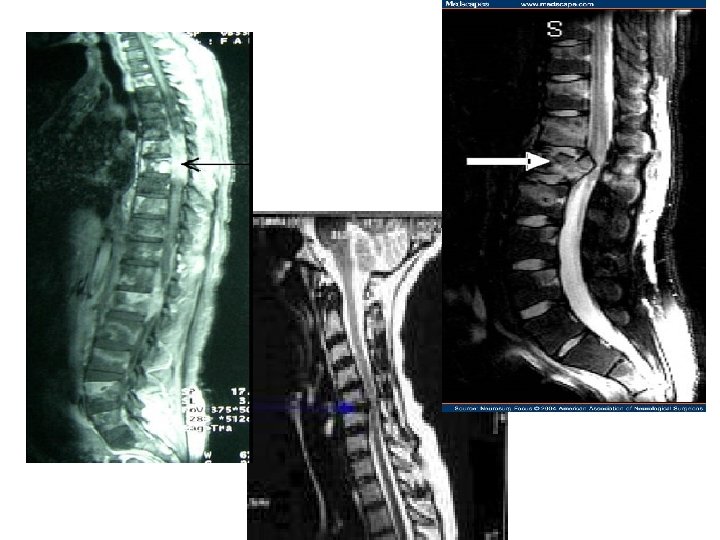

Investigations & information needed prior to Rx 1. MRI scan of the whole spine Ø 2. 3. 4. Knowledge of cancer type & stage Knowledge of patient fitness Current neurological function Ø Ø Ø 5. Can get compression at multiple levels Have they lost power in their legs? Can they walk? Do they need a catheter? Do they have pain?

MRI of spinal cord compression in a women with past history of breast cancer

Differential diagnosis • • Metastatic cancer Herniated disc Benign bony lesion Abscess Alcoholic neuropathy Primary tumour Osteoporosis Low potassium Case report 3/11 cases confirmed MSCC